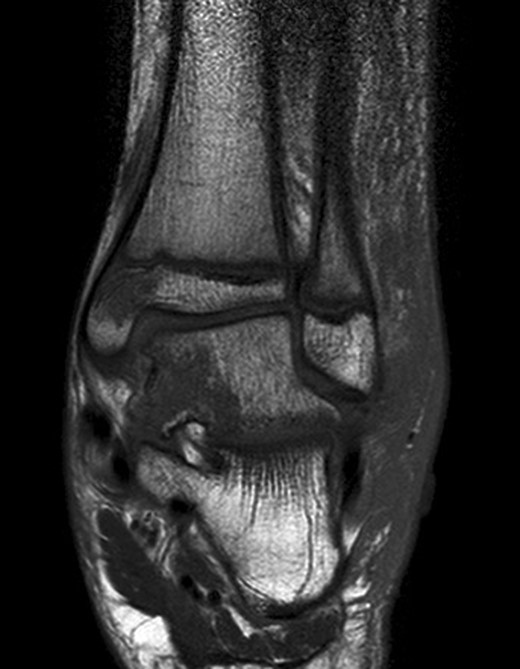

The patient subsequently underwent a manipulation under anaesthesia and POP application of his left distal tibia and right ankle to correct the talar displacement. Despite this, post-operative radiographs of the right ankle showed persistent widened medial tibio-talar joint, and the patient developed considerable right ankle pain and soft tissue swelling which did not correspond with the initial radiograph findings. Magnetic resonance imaging (MRI) of the right ankle joint was performed which revealed extensive marrow oedema through the medial malleolus epiphysis and the medial body of the talus. There was evidence of disruption of the medial cortex of the talus which explained the widened medial tibio-talar joint (Fig. 2). No disruptions of the epiphyseal plates or ligamentous structures were identified. The injury around the tibio-talar joint was identified as an undisplaced fracture through the postero-medial talus with a corresponding ‘kissing’-type lesion of the inner surface of the medial malleolus with gross soft tissue oedema. In view of the overlooked skeletal injury, a further computer tomography (CT) scan of the ankle joint was performed which confirmed a fragmented undisplaced fracture of the postero-medial aspect of the talus, with the anterior subtalar joint remaining intact and an undisplaced fracture through the medial malleolus (Fig. 3).

Right ankle MRI coronal view demonstrating bone marrow oedema in the medial malleolus and medial body of talus.